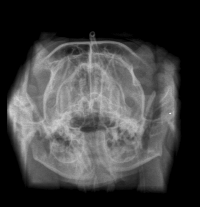

Oi pessoal… eu nunca imaginei precisar escrever isso, mas hoje estou pedindo ajuda para salvar o meu gatinho. Meu nome é Andressa e o Eren é meu companheiro, meu neném. Ele tem apenas 9 meses e sofreu um acidente que mudou tudo de repente. Levei ele às pressas para o hospital veterinário, onde chegou com dificuldade para respirar, muita dor e sangramento na boca, precisando ficar no oxigênio e ser internado imediatamente. Os exames mostraram que o impacto foi muito forte e causou uma luxação bilateral da mandíbula. Basicamente, a boquinha dele saiu do lugar dos dois lados. Desde então, ele não consegue fechar a boca direito, sente dor constante e não consegue se alimentar sozinho.Ver o Eren tentando comer e não conseguir é uma das coisas mais dolorosas que já vivi. Ele precisou passar por anestesia para tentar reposicionar a mandíbula e agora está com a boca imobilizada, usando focinheira por cerca de 20 dias e se alimentando através de uma sonda diretamente no esôfago. Mesmo assim, ainda existe a possibilidade de uma cirurgia mais complexa com ortopedista caso a mandíbula não permaneça no lugar. Foram dias de internação, exames, medicações fortes, monitoramento constante e cuidados intensivos, porque o trauma trouxe risco real à vida dele. Os custos estão aumentando a cada dia e infelizmente eu não estou conseguindo ter condições de arcar com tudo sozinha. Estou criando essa vaquinha porque quero dar ao Eren a chance de se recuperar e voltar a ter uma vida normal novamente e sem dor. Qualquer valor vai ajudar muito 🙏